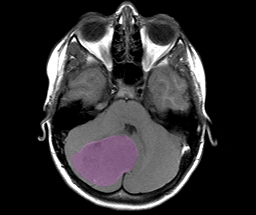

To be able to treat cancer of the central nervous system (CNS) successfully, it is important to have very precise knowledge about the molecular characteristics of the tumors in order to “give them the right name”. It is presently possible to differentiate about 100 types of CNS tumors based on tissue characteristics. These tumor types show widely varying responses to radiotherapy and chemotherapy. In some cases, methods of molecular diagnostics are used to further classify tumors, for example based on certain gene mutations. Nevertheless, their variability is large, which makes it difficult to standardize diagnostic methods.

The researchers analyzed specific chemical tags in the tumor genomes called DNA methylations. Different cell types exhibit characteristic patterns of DNA methylation which enable scientists to draw conclusions about a tumor’s cellular origin. "We have developed computer-based algorithms that reliably differentiate 82 types of CNS tumors based on their methylation patterns," said Professor David Capper, who is one of the four first authors of the study. Capper is a faculty member of the DKTK partner site in Berlin and has recently accepted a professorship for Molecular Neuropathology at Charité University Medicine Berlin. “Particularly in tumors which we cannot easily assign to a diagnostic category based solely on microscopic examination, methylation analysis is often helpful to make a precise diagnosis. The analysis of approximately 2,800 reference tumor samples additionally made it possible to classify tumors into specific subgroups that are not yet included in the classifications that have been used so far.”

In order to test whether the method is suitable for use in clinical routine diagnostics, the scientists analyzed more than 1,100 additional tumor samples. In about twelve percent of the cases, they were able to correct the initial diagnosis using the methylation patterns. In almost all cases where it was possible, further molecular-diagnostic examinations showed that molecular classification characterized the tumors even better than the initial microscopic diagnosis.